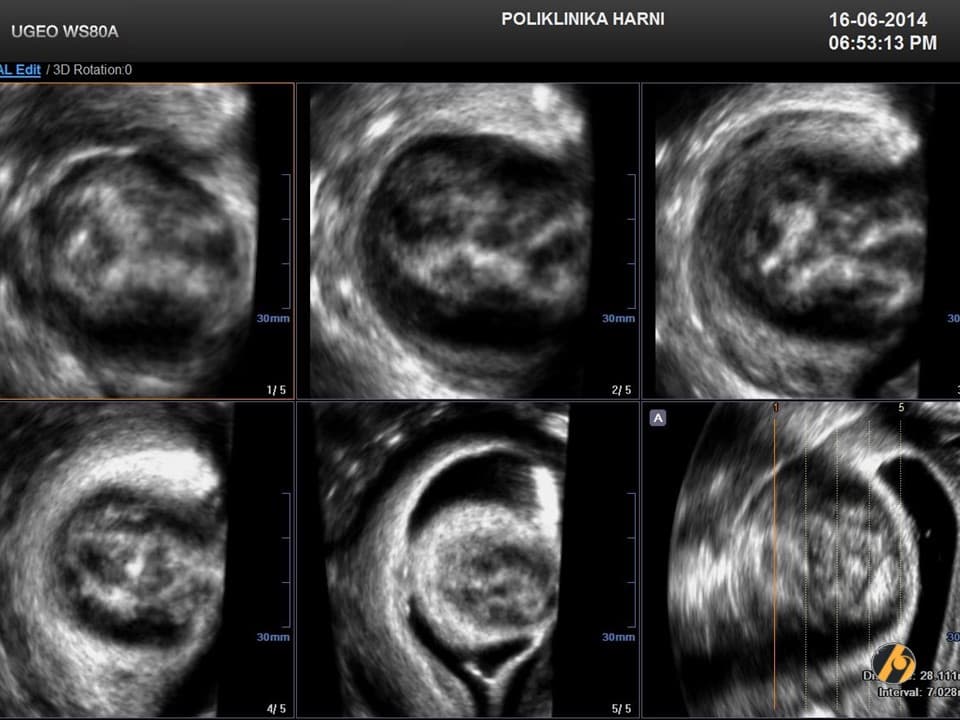

Dijagnoza

Dijagnoza mioma postavlja se temeljem anamnestičkih podataka, ginekološkog i ultrazvučnog pregleda. Ponekada su, osobito kod gigantskih mioma nužne dopunske metode kao što su intravenska urografija, CT ili MRI zdjelice, kako bi se u planiranju operativnog zahvata mogao procijeniti utjecaj mioma na okolne organe, a time i rizik povrede tih organa tijekom operacije.

Dijagnoza se postavlja ginekološkim pregledom i slikovnim pretragama.